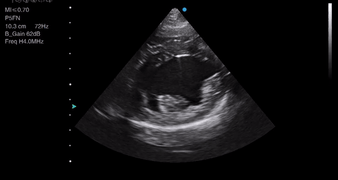

Video 1 demonstrates four views you can obtain with only a microconvex probe, from which you can begin to make a visual assessment of the size and function of a patient’s heart.

The first is not recognising an off-axis image (Videos 2A and 2B). The right parasternal long-axis views are the first views we obtain for dogs and cats and form the basis for the rest of the examination. If your long-axis views are off-axis, your short-axis ones will also suffer.

Another very common mistake is foreshortening (Video 3). This is where you have under- or over-rotated the image and are effectively somewhere between the long and short axis. For example, a dilated left ventricle may have a rounded appearance, but when visualised from the right parasternal long-axis or apical views, a normal left ventricle does not.

- Do you need to measure to tell which of these ventricles has increased wall thickness?